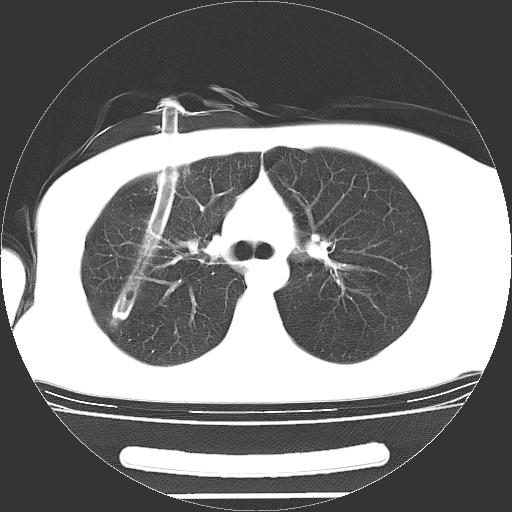

标题: CT19767:男,20岁,右侧气胸行闭式引流术后五天CT检查。 [打印本页]

男,20岁,右侧气胸行闭式引流术后五天ct检查看肺内是否有肺大泡,纵隔窗未见异常,未上传。

1)右侧胸腔闭式引流术后导管留置。2)右肺未见肺大泡。

未见肺大泡,还有微量气体。